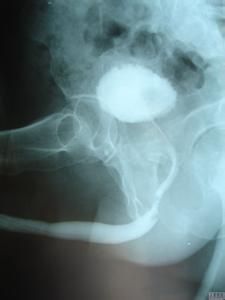

逆行法尿道造影

(四)具體操作方法及攝片位置

1.患者仰臥於x線工具機上,將導尿管插入尿道前端。將龜頭捏緊。或將注射器乳頭直接插入尿道外口,並緊靠尿道外口,阻止造影劑外溢。

2.然後使患者向任何一測傾斜45O臥,近床側腿彎曲,對側腿伸直。將陰莖拉直與身體長軸垂直。

3.放置膠片,對好管球。

4.在造影劑將注射完畢時曝光。